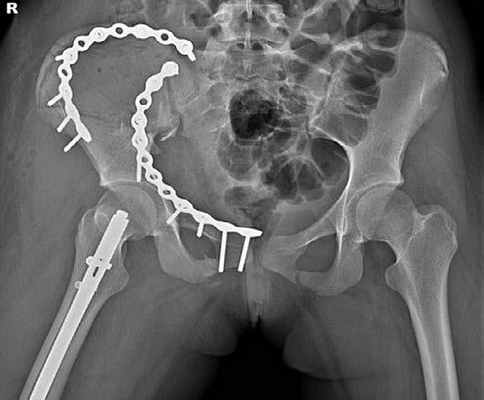

Клинический пример 1. Пациентка Р., 68 лет, травма в результате ДТП, пассажир. Доставлена бригадой скорой медицинской помощи (СМП). Установлен диагноз: политравма. Перелом боковых масс крестца справа Denis I. Перелом седалищной кости справа со смещением отломков. АО/ОТА — 61-В2.1 Перелом поперечных отростков слева L3–L5 (рис. 1). Рис. 1. Пациентка Р., 68 лет. Компьютерная томограмма, 3D-реконструкция, визуализирован перелом поперечных отростков слева L3–L5. Перелом боковых масс крестца слева Denis I. Закрытый перелом дистального метаэпифиза обеих костей правого предплечья со смещением отломков. Ушиб грудной клетки. По шкале ISS 21 балл.

После стабилизации состояния пациентки была предпринята попытка активизации. В связи с наличием ипсилатерального перелома верхней конечности и выраженного болевого синдрома в пояснично-крестцовой области на 3-и сутки одномоментно была выполнена фиксация крестца справа канюлированным винтом 7,0 мм. Остеосинтез костей предплечья был осуществлен пластинами и винтами. Пациентка была активизирована на 1-е сутки после операции. Послеоперационный период без осложнений.

Отдаленные результаты через 12 мес: на контрольных рентгенограммах определялись консолидированные переломы боковых масс крестца справа, седалищной кости справа (рис. 2). Рис. 2. Пациентка, Р. 68 лет. Рентгенография консолидированного перелома боковой массы крестца справа через 12 мес после операции. Остеосинтез канюлированным винтом. Консолидированный перелом седалищной кости справа. а — проекция: выход из таза; б — проекция: вход в таз. По шкале S. Majeed — 85 баллов, по тесту «Timed up & go» [30] 9 с (рис. 3). Рис. 3. Пациентка Р., 68 лет. а–в — внешний вид и функция через 12 мес после операции.